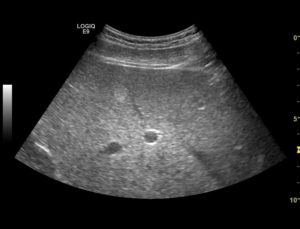

1.Увеличение размеров печени, как правой, так и левой ее доли 2.Контур печени остается ровным и четко видимым Только при выраженном гепатите, переходящем в цирроз отмечается неровность и нечеткость контура. 3.Нижний край печени становится более округлым 4.Повышается эхогенность ткани Причем, чем более выражен гепатит, тем больше эхогенность печени. Повышение эхогенности свидетельствует о том, что в ткани печени увеличивается количество плотной соединительной ткани. А это — признак любого хронического воспаления. 5.Неоднородность паренхимы Этот признак может долго отсутствовать, и появиться только на поздних стадиях развития болезни. Чем больше выражен процесс хронического воспаления, тем больше неоднородность ткани. 6.Постепенно обедняется сосудистый рисунок печени Происходит это потому, что становятся все хуже видны мелкие сосуды печени. Такой эффект объясняется тем, что более эхогенная, более светлая паренхима печени маскирует собой тонкие стенки мелких сосудов. 7.Обеднение сосудистого рисунка происходит за счет ухудшения видимости печеночных вен и мелких ветвей портальной вены Тогда как крупные ветви портальной вены, зачастую, видны более отчетливо. Этот эффект объясняется тем, что при некоторых формах хронического гепатита вокруг портальных сосудов идет более интенсивное разрастание соединительной ткани. При этом крупные ветви видны более четко, чем обычно. 8.Снижается звукопроводимость органа К такому эффекту приводит то, что при хроническом воспалении в паренхиме органа разрастается плотная соединительная ткань, которая плохо проводит ультразвуковые волны. О том, что такое звукопроводимость вы можете прочитать в статье «Что такое звукопроводимость?»

Ультразвуковое исследование при прогрессирующих хронических гепатитах В и С показывает разнородность паренхимы и ее крупнозернистую структуру. Поверхность органа становится дряблой, покрытой бугорками.

Такое явление характеризует и другие недуги – излишнее скопление липидов в тканях, цирроз, склерозирующий холангит (воспаление каналов отвода желчи). Хронический гепатит проявляется на УЗИ плохой визуализацией вен, сосудистый рисунок становится бледным.